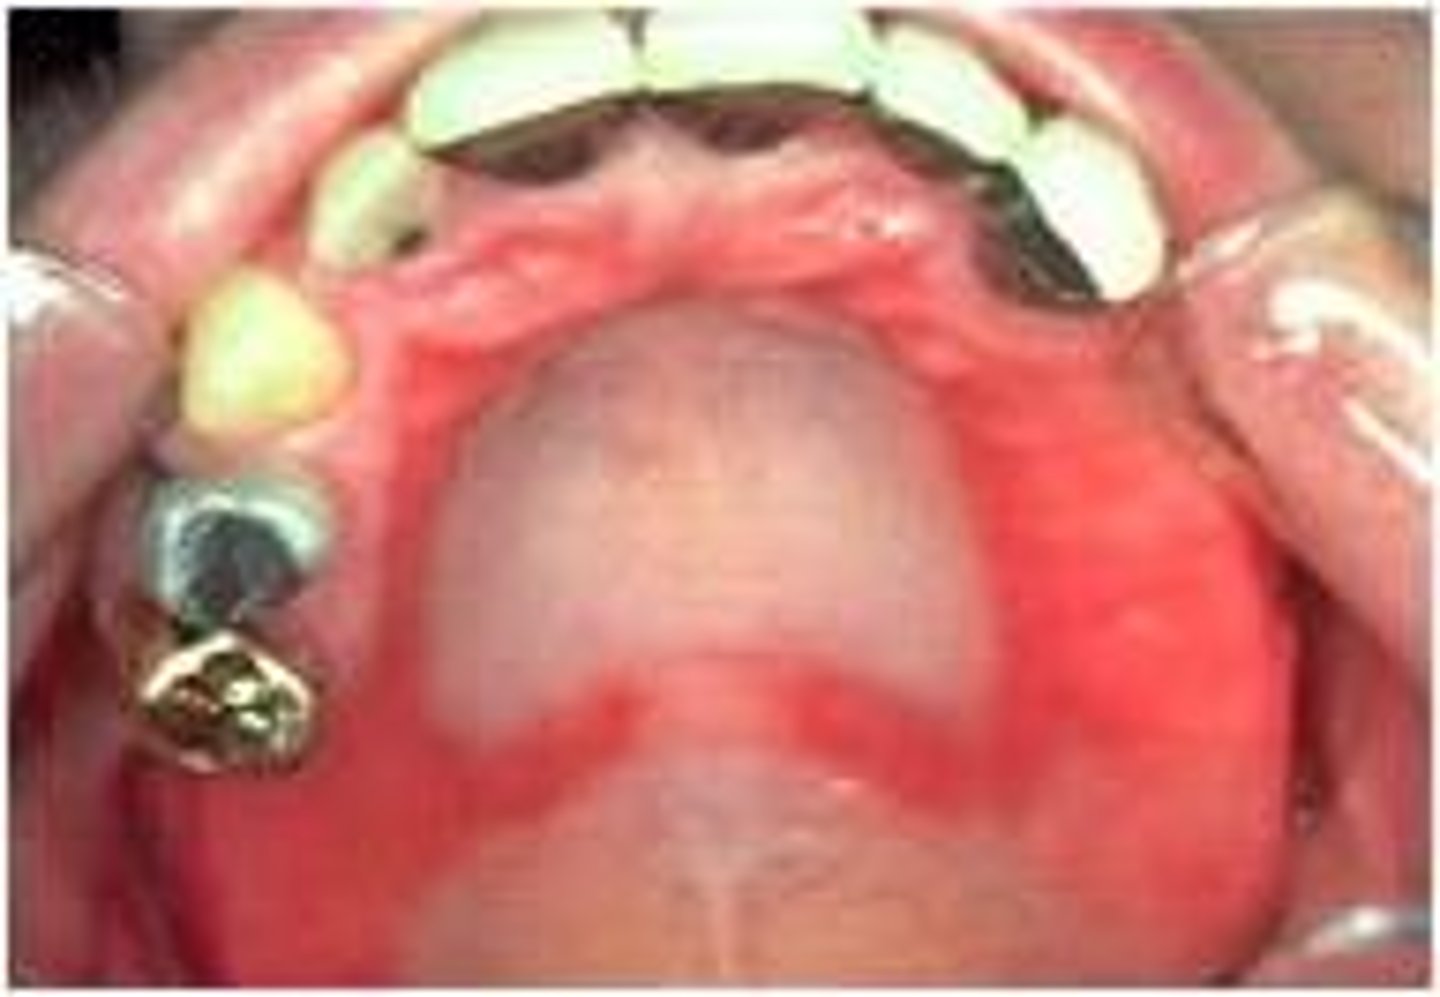

What is chronic atrophic candidiasis? (+ other name, common locations)

AKA Denture Stomatitis; well-defined red plaque under prosthesis

⢠common locations: palate, maxillary ridge

⢠no pain